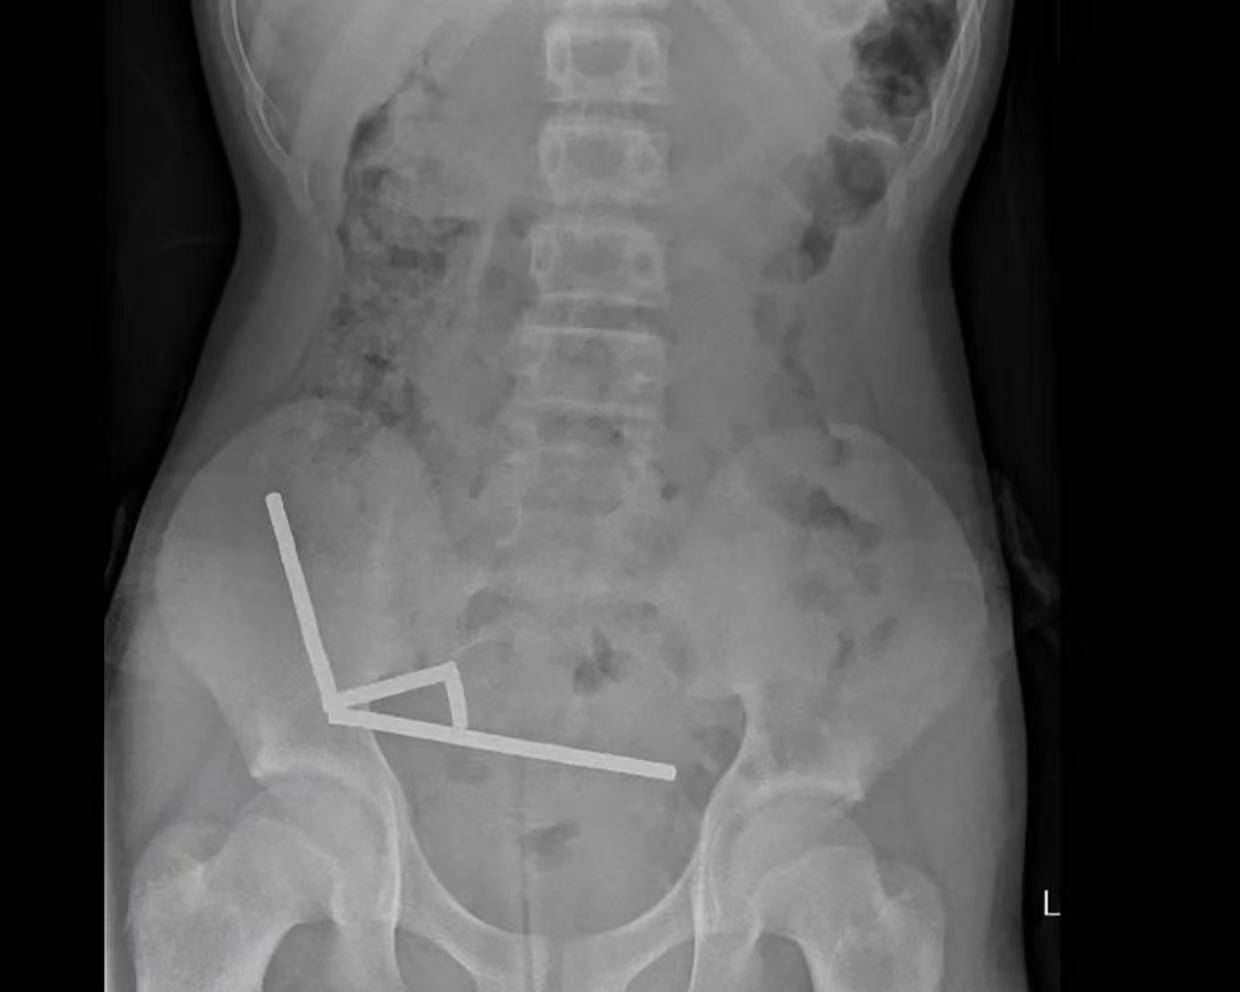

▲X光显示皇冠信用網出租代理 ,磁铁在男孩体内紧密吸附成链状结构

据悉,这名未透露姓名的少年在持续腹痛4天后被送往新西兰北岛的一家医院皇冠信用網出租代理 。医生通过X光检查发现,这些磁铁在他的肠道内互相吸附,形成了四条链状结构。